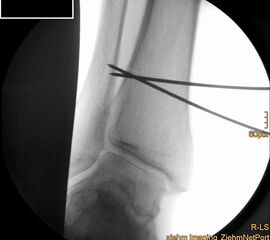

Auch hier wird die Korrektur im CORA (Center oft Rotation and Angulation) durchgeführt. Primär werden intraoperativ unter Bildwandler Kontrolle Kirschner Drähte als Sägelehre konvergierend eingebracht. Dann wird der geplante medialbasige Keil mit der oszillierenden Säge entfernt. Die laterale Kortikalis sollte geschont werden, sie dient als Drehpunkt für die Osteotomie. Die Osteosynthese kann dann im Sinne einer Zuggurtung ein besonders stabiles Konstrukt bilden. Liegen mehrdimensionale Deformitäten vor, die eine Korrektur in Translations- und Rotationsebene erfordern, ist eine Durchtrennung der lateralen Kortikalis notwendig, ebenso bei ausgedehnten Korrekturen mit Keilhöhen über 10mm 218.